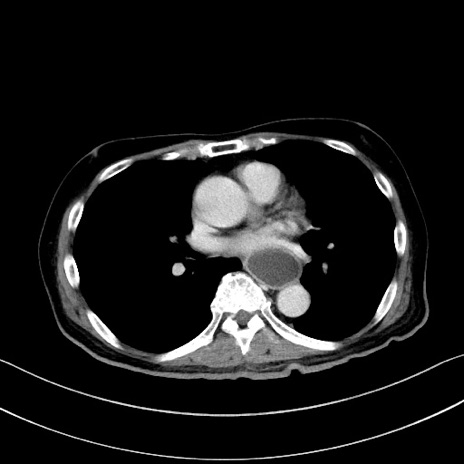

症例28(横断像)

【症例】60歳代男性

【主訴】嘔吐

【現病歴】胃癌にて胃全摘後。食思不振が悪化し、夜中に嘔吐することがある。

【既往歴】胃癌、胃全摘、脾摘、胆摘後

【データ】WBC 5900、CRP 10.56